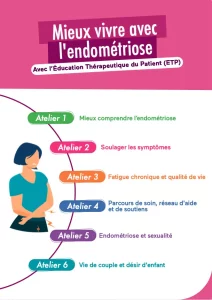

L’Union des URPS, coordonnée par l’URPS SF HdF avec le soutien d’EndoFrance, EndoMind et l’ARS des Hauts de France a pu réunir sages femmes, médecins, infirmiers, kinésithérapeute pharmacien, diététiciens, psychologues et sexologues afin de créer un programme d’ETP « Mieux vivre avec l’Endométriose ».

Avec la reconnaissance croissante de l’endométriose comme une maladie chronique pouvant avoir un impact profond sur la vie des femmes, l’éducation thérapeutique s’est rapidement présentée comme un outil essentiel pour permettre de les accompagner au mieux dans la compréhension et la gestion de leur maladie afin d’améliorer leur qualité de vie – et renforcer leur pouvoir d’agir.